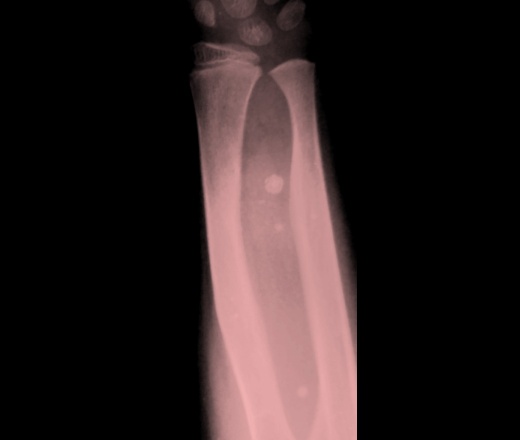

Флеболиты могут вызвать акустические тени в 20-67% случаях при кавернозных гемангиомах. Другие модели включают криволинейные или аморфные кальцификации. Гемангиомы расположенные близко к кости, могут вызывать периостальную реакцию, которая обычно зрелая и неагрессивная. Кортикальное утолщение или эрозия на УЗИ опухоли встречается реже. Рентгенограммы могут показать участки кальцификации мягких тканей.

При контролях в динамике - мягкотканный компонент с наличием округлых теней.

Округлые плотные тени - флеболиты.

- Часто - образование кальцинатов (до 50% случаев), что приводит к образованию флеболитов.